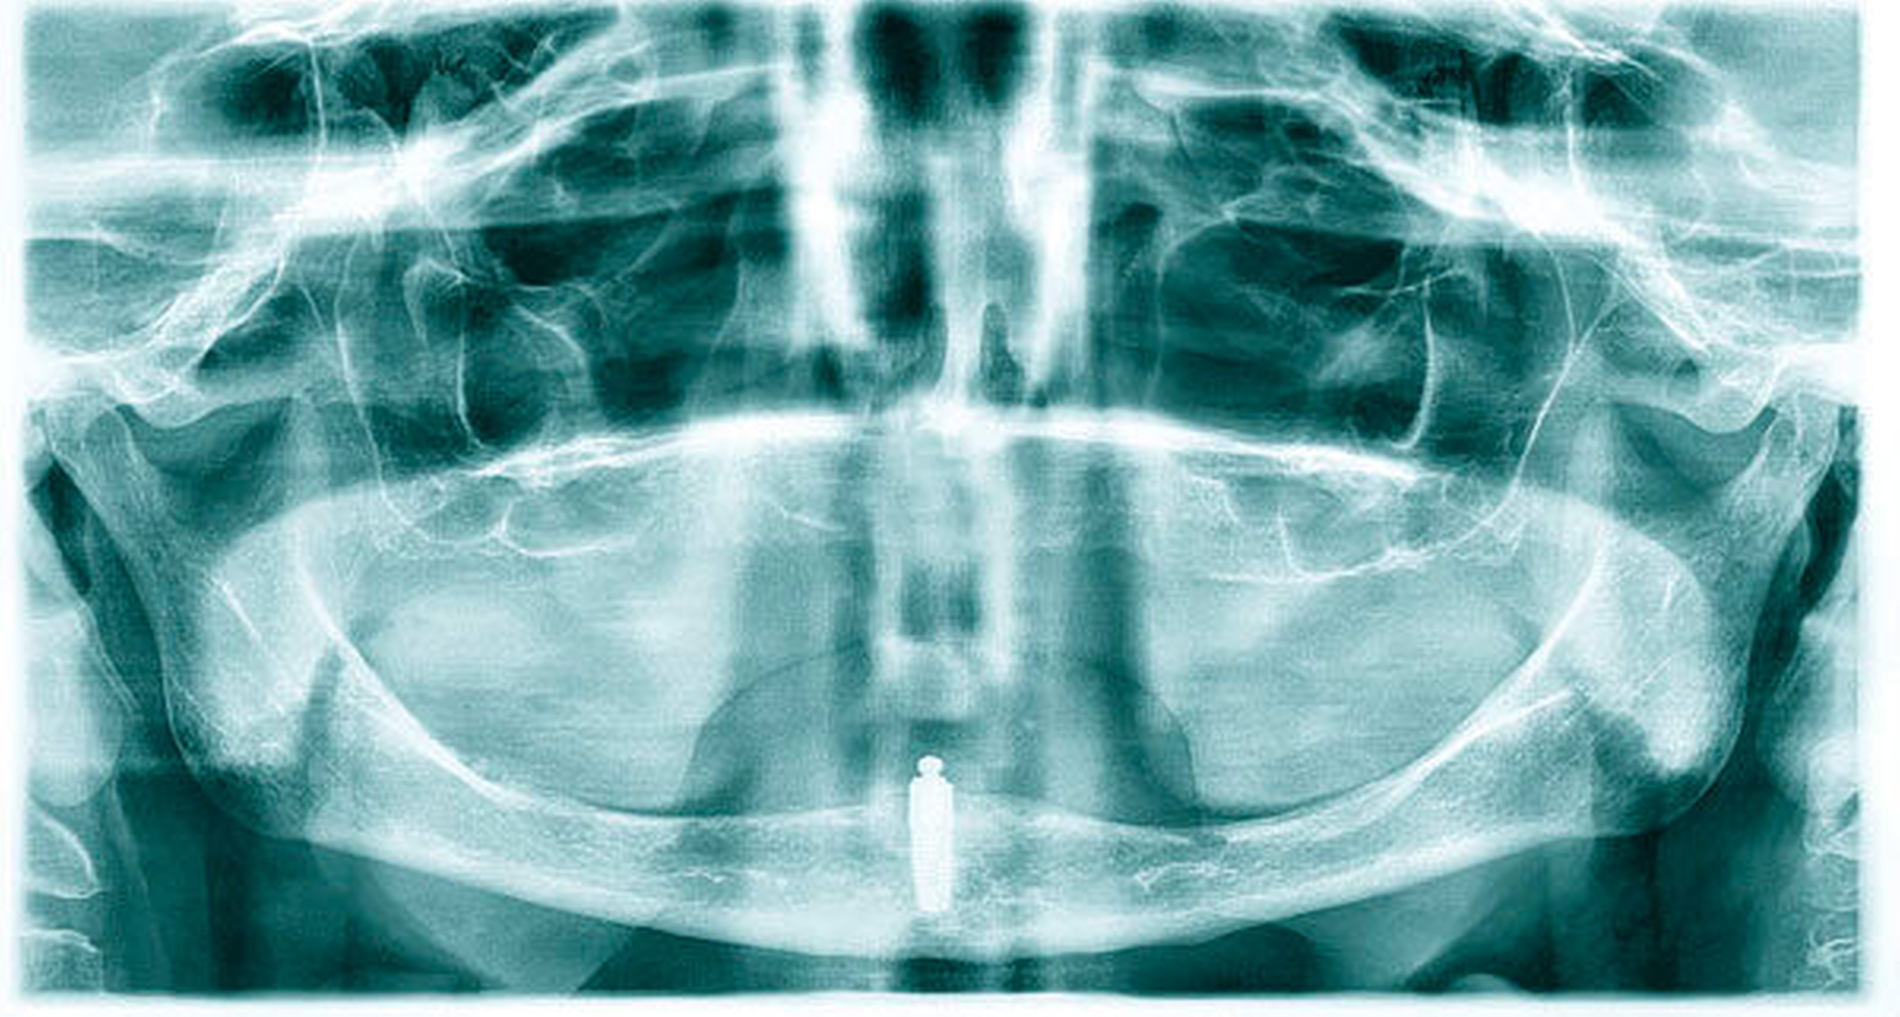

Untersucht wurden im Rahmen der Studie insgesamt 158 Patienten. Randomisiert wurden die Studienteilnehmer entweder der Gruppe mit Sofortbelastung des Implantats (n = 81) oder der Gruppe mit verzögerter Belastung nach drei Monaten Einheilungszeit (n = 77) zugeordnet. Voraussetzungen zur Teilnahme an der Studie waren (unter anderem) eine ausreichende Knochenhöhe von 11 bis 20 mm, keine Kontraindikationen für Implantate, ein Knochenlager, das keiner Augmentation bedarf, eine vorhandene, suffiziente Totalprothese im Ober- sowie im Unterkiefer mit bilateral balancierter Okklusion, die seit mindestens drei Monaten in situ ist, aber einen mangelhaften Halt im Unterkiefer aufweist. Für die präoperative Bildgebung wurde mithilfe einer Röntgenmesskugel, adjustiert an der Unterkieferprothese mit einem Durchmesser von 4 mm, eine Panoramaschichtaufnahme erstellt und das Knochenlager entsprechend für das Setzen eines enossalen Implantats (Camlog Screw Line, Camolg Biotechnologies, Wimsheim, Länge 13 mm, Durchmessser 3,8 mm) beurteilt (Abbildungen 1 und 2). Die Implantation folgte dem üblichen Vorgehen mit den zugehörigen Bohrern des Camlogsystems. Die Primärstabilität des Implantats wurde anhand des Osstell-Geräts (Osstell, Grothenburg, Schweden) beurteilt.

Anschließend sollte eine röntgenologische Kontrolle mittels Panoramaschichtaufnahme erfolgen. Nach einer Implantateinheilung von drei Monaten können chairside die Retentionselemente in den vorhandenen Zahnersatz eingearbeitet werden. Das Kugelkopfattachment (Gingivahöhe 1,5 mm, Camlog) wird mit einem manuellen Drehmomentschlüssel (Camlog) mit einem definierten Drehmoment von 30 Ncm eingesetzt (Abbildung 3).